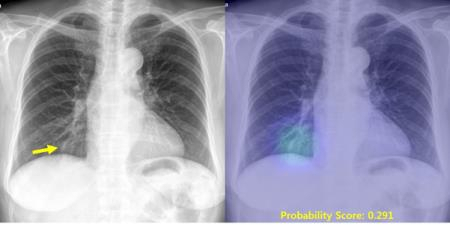

연구팀은 "인공지능 시스템은 환자의 흉부 X-선 영상을 분석해 이상 소견이 있는 부위를 표시하고, 그 가능성을 확률값으로 제시해 준다"면서 "이를 통해 보다 손쉽게 영상진단을 내릴 수 있게 된다"고 말했다.